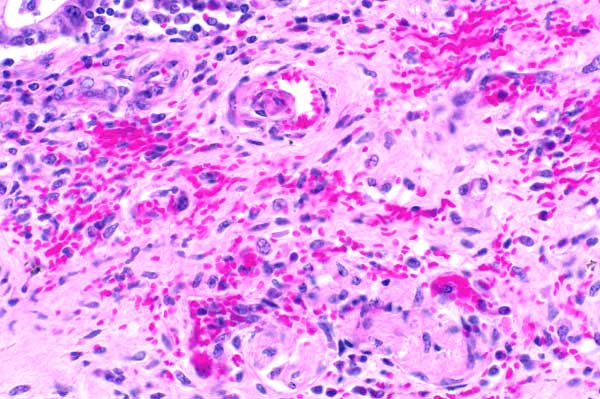

20x   |   Hematoxylin and Eosin

Within the submucusa, there is multifocal hemorrhage.